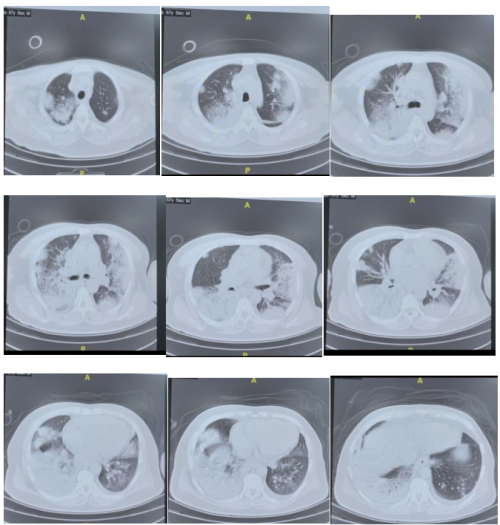

胸部CT变化:

12月2日: